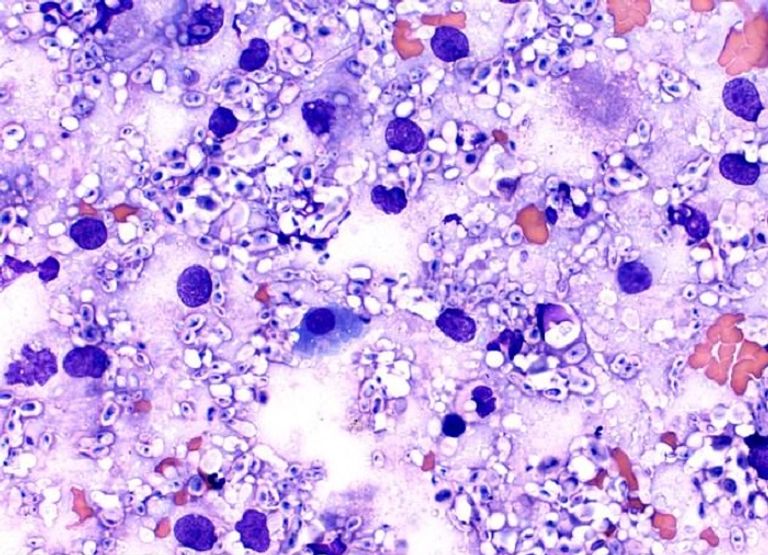

وأوضحت الصحيفة أن العلماء اكتشفوا أن هذه الفطريات تنمو فعليًا في مناطق الإشعاع، كما لو كانت تنجذب إليها، وأن الكميات الكبيرة من الميلانين (الصبغة المسؤولة عن تحول لون البشرة إلى اللون الداكن) التي يمتلكها الفطر تمكنه من امتصاص الأشعة الضارة التي تتحول بعد ذلك إلى طاقة كيميائية.

وبالطريقة نفسها التي تحول بها النباتات ثاني أكسيد الكربون والكلوروفيل إلى أكسجين والجلوكوز عن طريق التمثيل الضوئي، تمتص هذه الفطريات الأشعة المميتة وتحولها إلى طاقة.